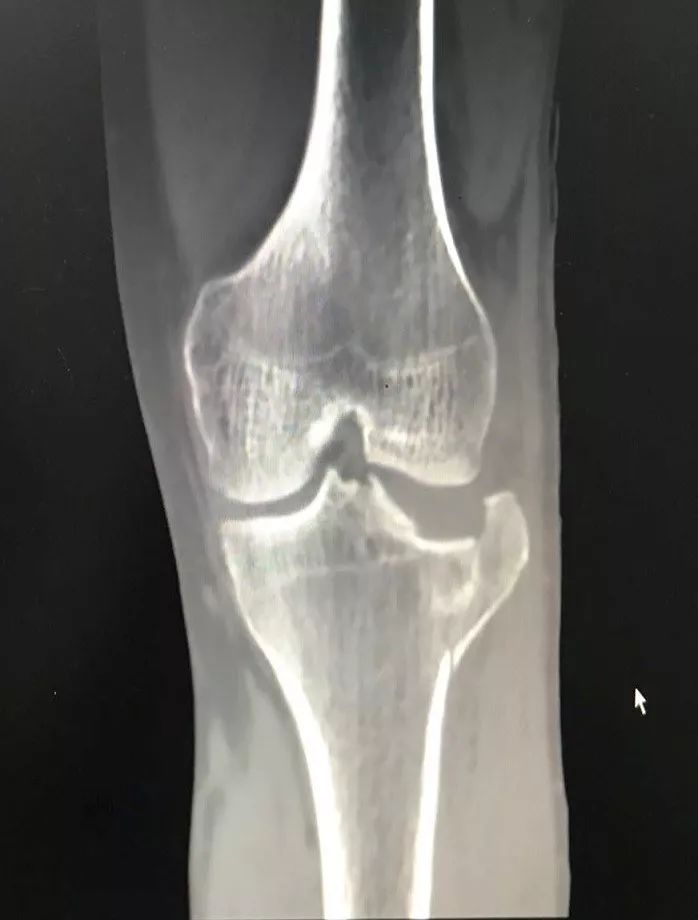

术前摄片(左)VS术后摄片(右)

“这在以前是不可想象的!像王先生这样严重塌陷的胫骨平台骨折,常规的手术方法需要大约15厘米的手术刀口,再放入长钢板固定。手术创伤大,随之而来的是剧烈的术后疼痛,漫长的恢复时间,昂贵的手术费用。对于患者,就意味着更大的经济损失和精神痛苦。”沈主任介绍说。